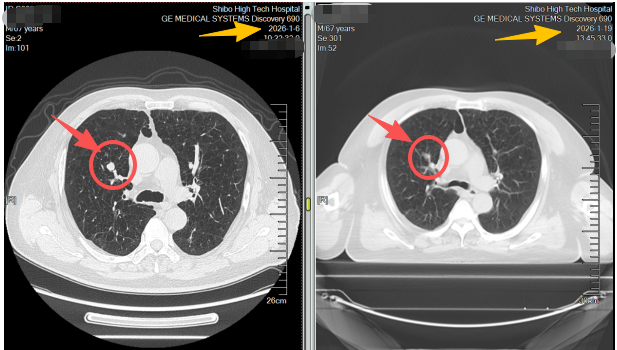

不同于传统放疗需数十次照射、持续一两个月,患者进需要数次的射波刀治疗,全程无切口、无出血、无需麻醉,每次治疗约30分钟,结束后即可自主离院。治疗两周后复查CT,影像结果令人振奋:原本的肺结节病灶基本消失,周围正常肺组织无任何损伤,患者身体状态良好,无明显不适症状。